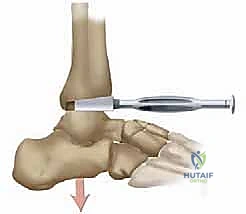

5. Final Tibial Component Impaction & Fixation: The final tibial component is then impacted with its specific impaction tool, ensuring it is fully seated. Through the designated screw hole in the tibial component, we advance a 2.5-mm drill through the posterior tibial cortex. A specially designed polyethylene sleeve is then placed into this screw hole, and a 4.0-mm AO small fragment cancellous screw is inserted to secure the tibial component to the tibia. This screw fixation is crucial for limiting initial micromotion and promoting effective bone ingrowth in uncemented implants. For osteopenic patients, we routinely use bone cement for fixation.

TECH FIG 4 • Trial and setting. C. Screw fixation.

6. Final Talar Component Impaction: With the ankle held in plantarflexion, the final talar component is then impacted using its dedicated talar impactor, ensuring it is fully seated and stable.

TECH FIG 4 • Trial and setting. D. Implantation is completed.